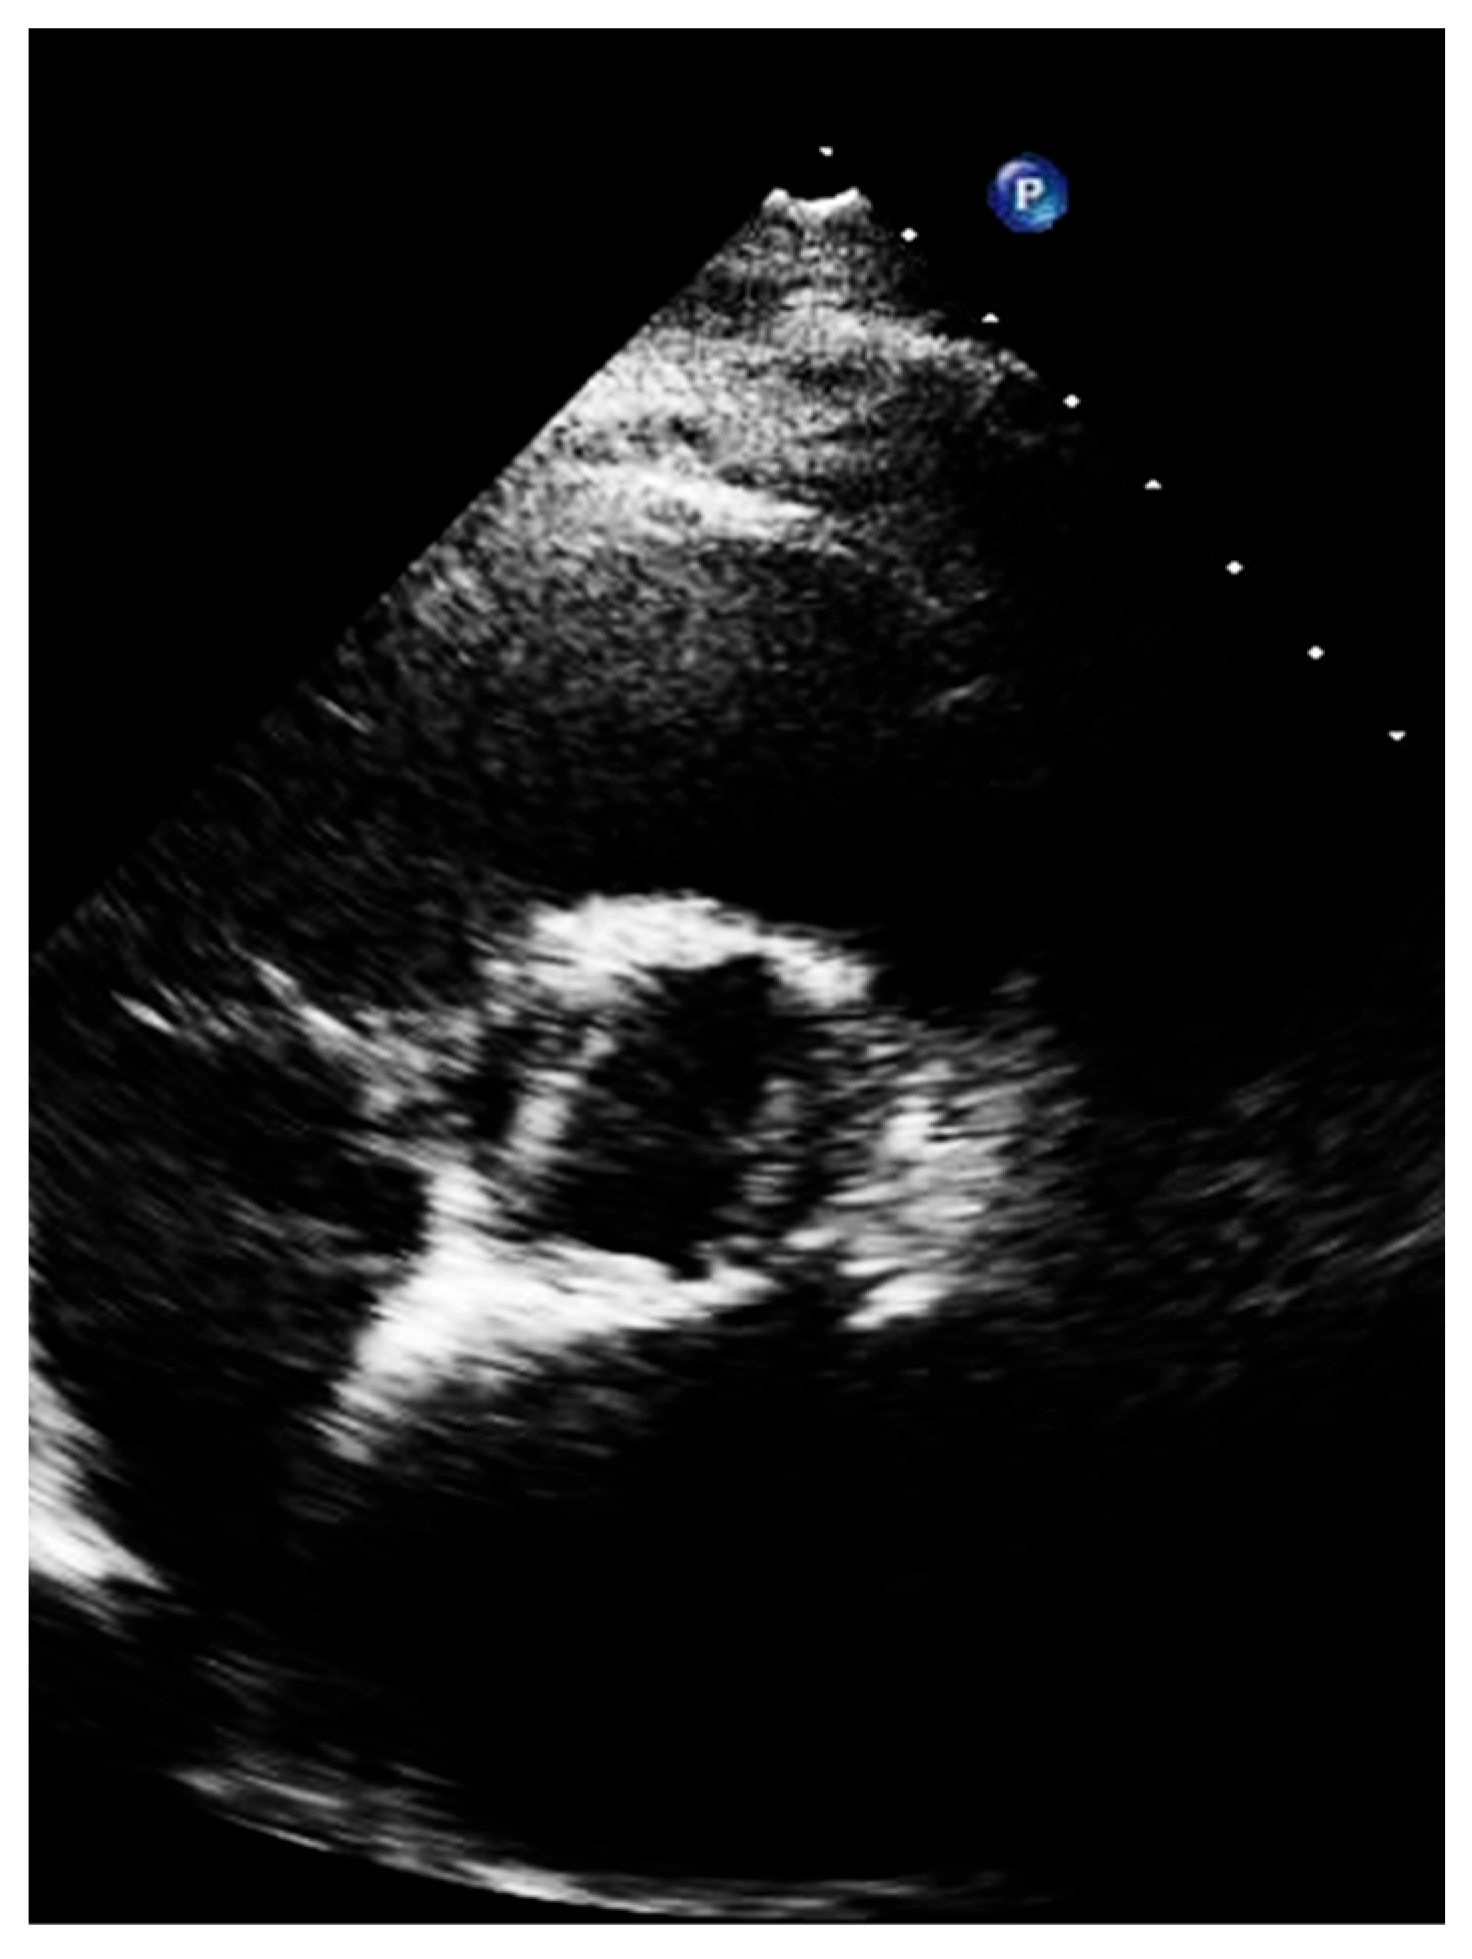

2. Long Axis View